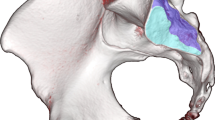

Graphical Abstract

In addition to the features that were scored semi-quantitatively and quantitatively, some obvious other incidental findings were depicted on CT as well as on sCT, such as spina bifida occulta (2 cases), ossification centers of the apophysis of the iliac crest (4 cases) and an enostoma (1 case) (Fig. 1).

Some incidental findings were seen on both MRI-based synthetic CT (sCT) (left images a, c, and e) and CT (right images b, d, and f). a–b Spina bifida occulta of S1 (arrowhead) in a 15-year-old girl in an axial plane. Also note the ossification centers of the apophysis of the iliac crest that can be seen as well (arrows). c–d Lumbosacral transitional anomaly without bony fusion on the left side (asterisk) in a 12-year-old boy in a paracoronal plane. Also note the white line in the right SI joint (black arrowhead), consistent with an artifact on sCT (this was not seen on CT). e–f Enostoma in a 16-year-old female on the left side of S1 in a paracoronal plane (black arrows)

Ankylosis and bony bridges of the SI joint are known structural lesions in sacroiliitis [3, 4, 10], however they were not expected in this normal population. In our study, bony bridges were scored in only 1 patient on sCT on the left side, not on CT, resulting in a kappa value of 0 (Table 3) (Table S1). Bony bridge-like features are a known artifact on sCT and a potential pitfall that has already been described in adults when using sCT for the diagnosis of sacroiliitis. Morbée et al. have shown that the vacuum phenomenon can be falsely seen as the bony bridge on sCT in SI joints [21]. In our case too, this rather thin white “artifactual” line crossing the SI joint on sCT (Fig. 1b.) did not mimic true ankylosis as can be seen in sacroiliitis, also no other features of sacroiliitis were present. In our normal study group, we also detected an incidental enostoma (Fig. 1e–f.) near the SI joint, which was equally seen on CT and sCT. This is promising as sCT might be used as well for assessing sclerosis as a structural lesion of sacroiliitis [21].